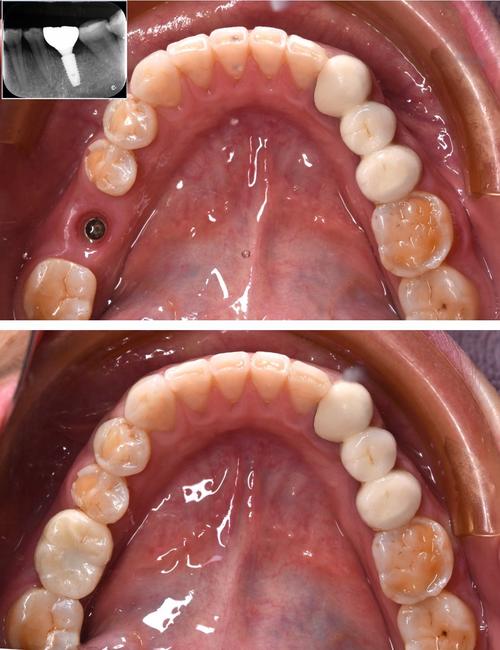

基台安装与牙冠制作(1-2周)

骨结合完成后,医生在种植体上安装基台(连接种植体与牙冠的中间结构),并取模制作个性化牙冠,牙冠材料可选择全瓷(美观、生物相容性好)或烤瓷(强度高、性价比高),医生会根据患者咬合、邻牙颜色调整牙冠形态与色泽,确保自然协调。

最终佩戴与维护(长期)

牙冠安装完成后,医生会调整咬合,确保受力均匀,患者需适应1-2周,期间若有不适(如咬合高点)及时复诊,种植牙虽耐用,但仍需日常维护:使用软毛牙刷、牙线清洁,避免咬硬物(如坚果、螃蟹壳),每半年至1年进行专业洁牙和种植体周围检查,预防种植体周围炎(可能导致种植失败)。